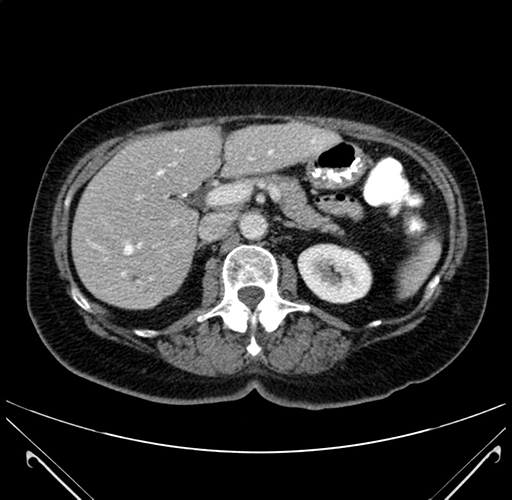

Pre-Chemo: Axial Venous